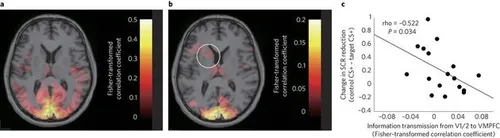

De angst (in kleur) voor en na de nieuwe therapie.

Volgens de onderzoekers was dit een effectief middel om de mensen van hun nieuwe fobie af te helpen. Na die drie dagen was er zo goed als geen hersenactiviteit in die ellendige amygdala meer te zien. Dat is het beste resultaat waar wij als angstigen op kunnen hopen: het zou betekenen dat als deze therapie ook op grotere schaal en met wellicht dieper liggende angsten werkt we onszelf kunnen genezen van de angsten zonder eerst door de hel van aversietherapie te moeten gaan of zelfs medicatie te moeten gebruiken. Als dat geen doorbraak is weten wij het ook niet meer.